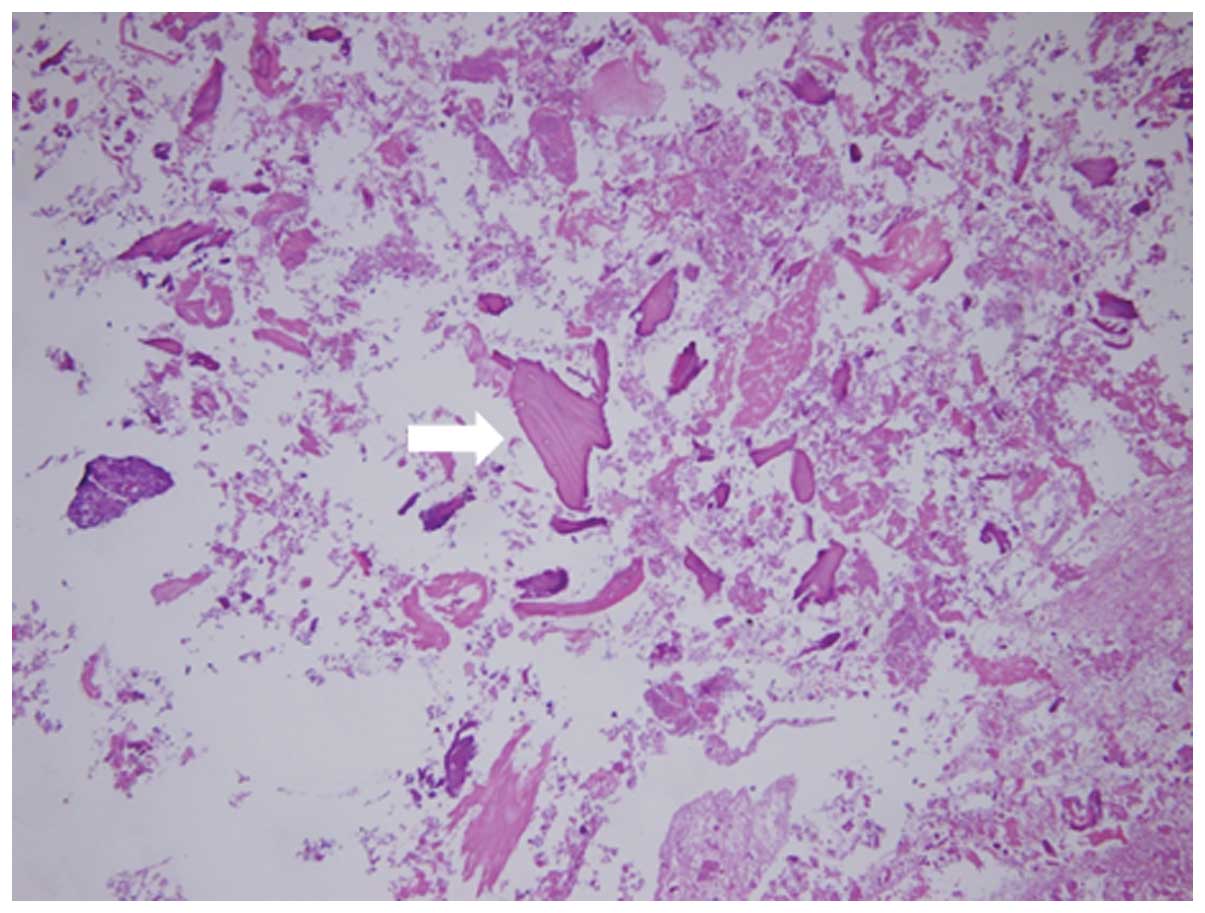

Surgical excision was carried out via an anterior approach. The cystic black-brown fluid with the fibrinoid necrotic tissue had erupted. The contents of the cyst were resected, and partial bursal excision was performed. Following the partial bursal excision, total hip arthroplasty (THA) was performed using the Hardinge approach. The contents of the bursa were stained with hematoxylin and eosin. The uptake of bone cartilage debris and fibrinoid necrosis deposition was apparent (Fig. 2). This content of the bursa has the same structure as the synovial tissue of the hip joint.

Figure 2.

Histological appearance of the synovial fluid in the contents of the bursa (hematoxylin and eosin staining; magnification, ×100). Bone and cartilage debris and fibrinoid necrosis depositions were apparent (white arrow).